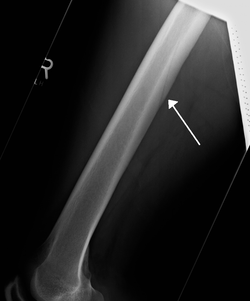

![]() A nutrient artery feeding the femur seen on X-ray | |

The medullary or nutrient artery (arteria nutricia), usually accompanied by one or two veins, sends branches upward and downward to the bone marrow, which ramify in the medullary membrane, and give twigs to the adjoining canals. Nutrient arteries are the most apparent blood vessels of the bones.

All bones possess larger or smaller foramina for the entrance of the nourishing blood-vessels; these are known as the nutrient foramina, and are particularly large in the shafts of the larger long bones, where they lead into a nutrient canal, which extends into the medullary cavity.[1]